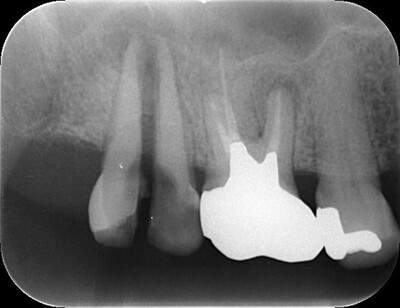

歯根破折①

歯根破折

歯根(歯の根っこの部分)まで縦に割れる、または亀裂が入る事です。

歯根は歯を支える骨の中に埋まっているため、縦に割れる、亀裂が入ると歯科材料での修復が困難になります。ほとんどの場合が抜歯になります。